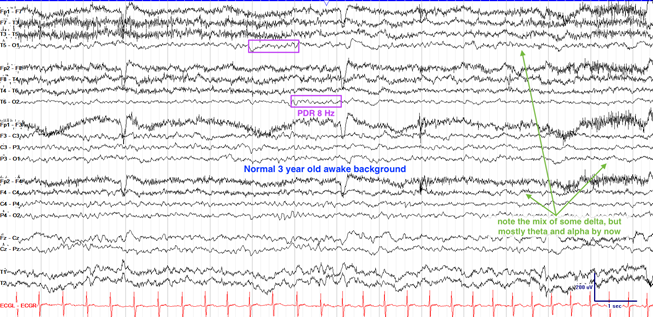

3岁后头部优势节律(PDR)达到8Hz

儿童EEG的成熟遵循“后向前”梯度,枕区节律发育最早:

幼儿期(1–3岁):后头部α节律(8–10 Hz)开始形成,但稳定性差

学龄期(>6岁):α频率增至9–12 Hz,θ波占比下降,前头部β活动(>13 Hz)逐渐显著。